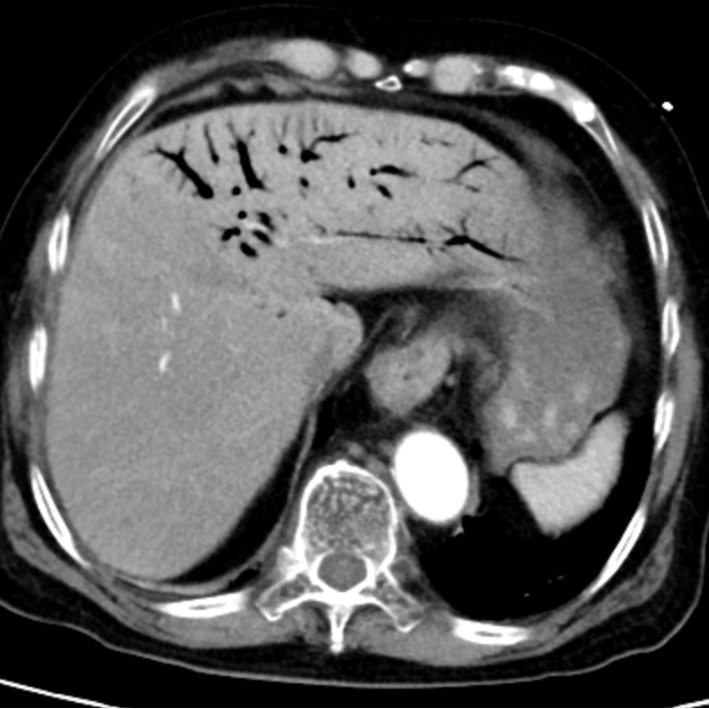

急诊CT结果让医护人员高度警惕:肝门静脉及肠系膜静脉广泛积气。

肝脏内血管广泛积气